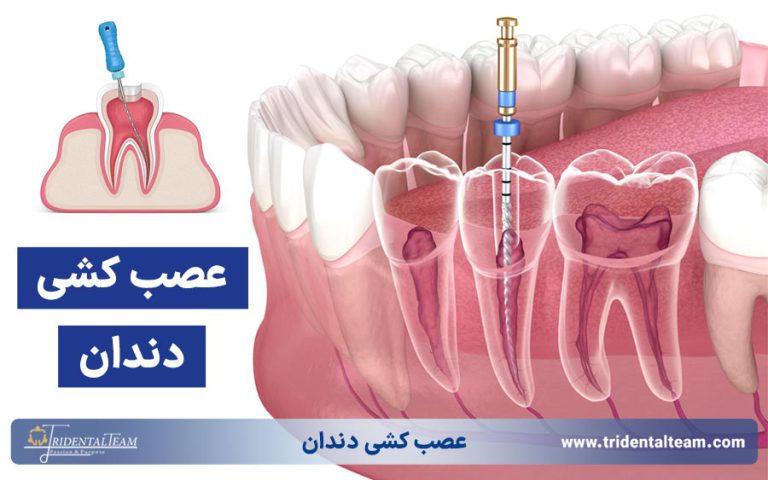

عصب کشی و درمان ریشه در تجریش

برای درمان تخصصی عصب کشی و ریشه در تجریش، کلینیک ترایدنتال با تیم مجرب و تجهیزات پیشرفته آماده خدمت رسانی است. درمان بدون درد و موثر با ضمانت کیفیت، نتیجه ای مطمئن و ماندگار را برای شما به همراه دارد. سلامت دندان های خود را به ما بسپارید.

علاوه بر درمان های زیبایی، کلینیک تریدنتال در حوزه دندانپزشکی عمومی نیز بهترین خدمات را با استفاده از مواد درجه یک و روش های پیشرفته ارائه می دهد. از درمان ریشه دندان، جرم گیری دندان، انواع ترمیم های دندانی، روکش دندان، جراحی دندان عقل و جراحی لثه گرفته تا بریج و سایر درمان های تخصصی، تمامی خدمات در محیطی آرام و با رعایت استانداردهای جهانی انجام میشود. اگر به دنبال تجربه ای بدون دردسر، همراه با دقت، ظرافت و بالاترین کیفیت توسط بهترین متخصصان دندانپزشکی در شمال تهران هستید، کلینیک تریدنتال بهترین گزینه برای شما خواهد بود. کلینیک تریدنتال با حضور بهترین دندانپزشک در تجریش، محیطی مطمئن برای دریافت خدمات دندانپزشکی زیبایی و عمومی فراهم کرده است.

در تریدنتال، بهترین کلینیک دندانپزشکی تجریش، هر درمان دندانپزشکی توسط متخصص مربوط به آن انجام میشود تا بیماران بالاترین کیفیت خدمات را با مناسب ترین قیمت دندانپزشکی دریافت کنند. تیم و پرسنل حرفه ای این مجموعه شامل دکتر امیر بهرامی، ایمپلنتولوژیست مجرب که در زمینه کاشت ایمپلنت های دندانی تخصص دارد، دکتر هانیه حقیقی، متخصص زیبایی دندان که با مهارت بالا در زمینه لمینت، کامپوزیت و اصلاح طرح لبخند فعالیت میکند و دکتر مریم حقیقی، متخصص ریشه دندان که درمانهای ریشه و عصب کشی دندان را با دقت و بدون درد انجام میدهد، تشکیل شده است. اگر به دنبال دندانپزشک در تجریش هستید که تجربه و تخصص را در کنار جدیدترین روش های درمانی ارائه دهد، کلینیک تریدنتال بهترین گزینه برای شماست. در این مرکز، هر بیمار تحت نظر بهترین دندانپزشک در تجریش و بر اساس نیازهای فردی خود درمان میشود تا لبخندی سالم و زیبا داشته باشد.